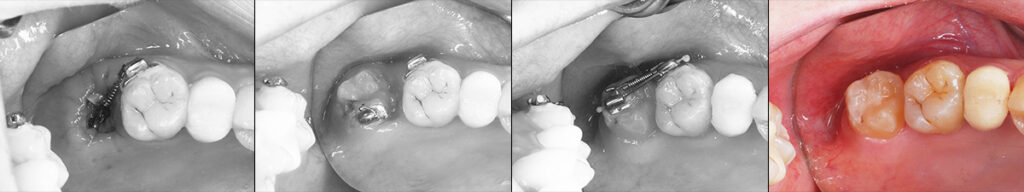

世代が上がれば後方の90度変位した埋伏智歯の移植利用を考えるが歯髄失活は免れないため、困難な矯正であるが萌出間もない大臼歯として今後を託せる生活歯のまま保存する。 矯正用のアンカースクリューと各種装置を智歯に接着させ、移動の各段階で交換しながら抜歯した第二大臼歯部に誘導する。 第一大臼歯は保存治療後ジルコニアセラミック冠で歯冠修復し約7年経過。 治療期間は 2017/12~2019/03

前方大臼歯抜歯時に矯正用アンカーを歯槽骨にねじ込み、引張用のアタッチメントを智歯歯冠に接着

矯正力のかけ方は智歯の萌出状態によって変更

左:治療開始時2017/12 右:健診時2023/07